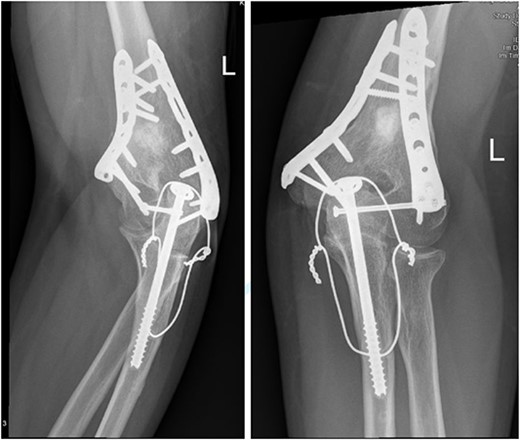

A 14-year-old boy with unknown medical and surgical history was brought by the emergency medical services to the emergency department as a case of multiple trauma after a MVA. Upon arrival, primary and secondary surveys were conducted, and management followed accordingly. After stabilization, all related specialties were involved in case management. Multiple fractures were detected, including left mandible, acetabular, open femur, and humerus fractures, as well as a comminuted pelvic fracture. The humerus fractures involved the proximal and distal area, as shown in Fig. 1.

Anteroposterior (AP) view of the left humerus and elbow pre-operative.